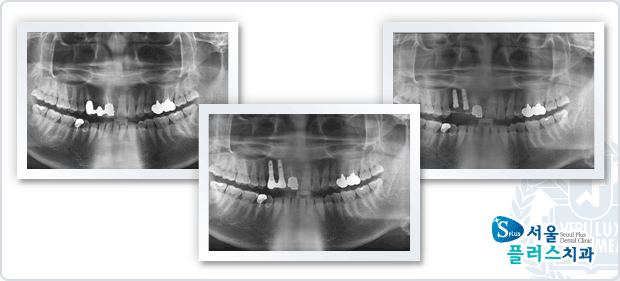

[임플란트] 임플란트 - 상악 전치부 임플란트 식립